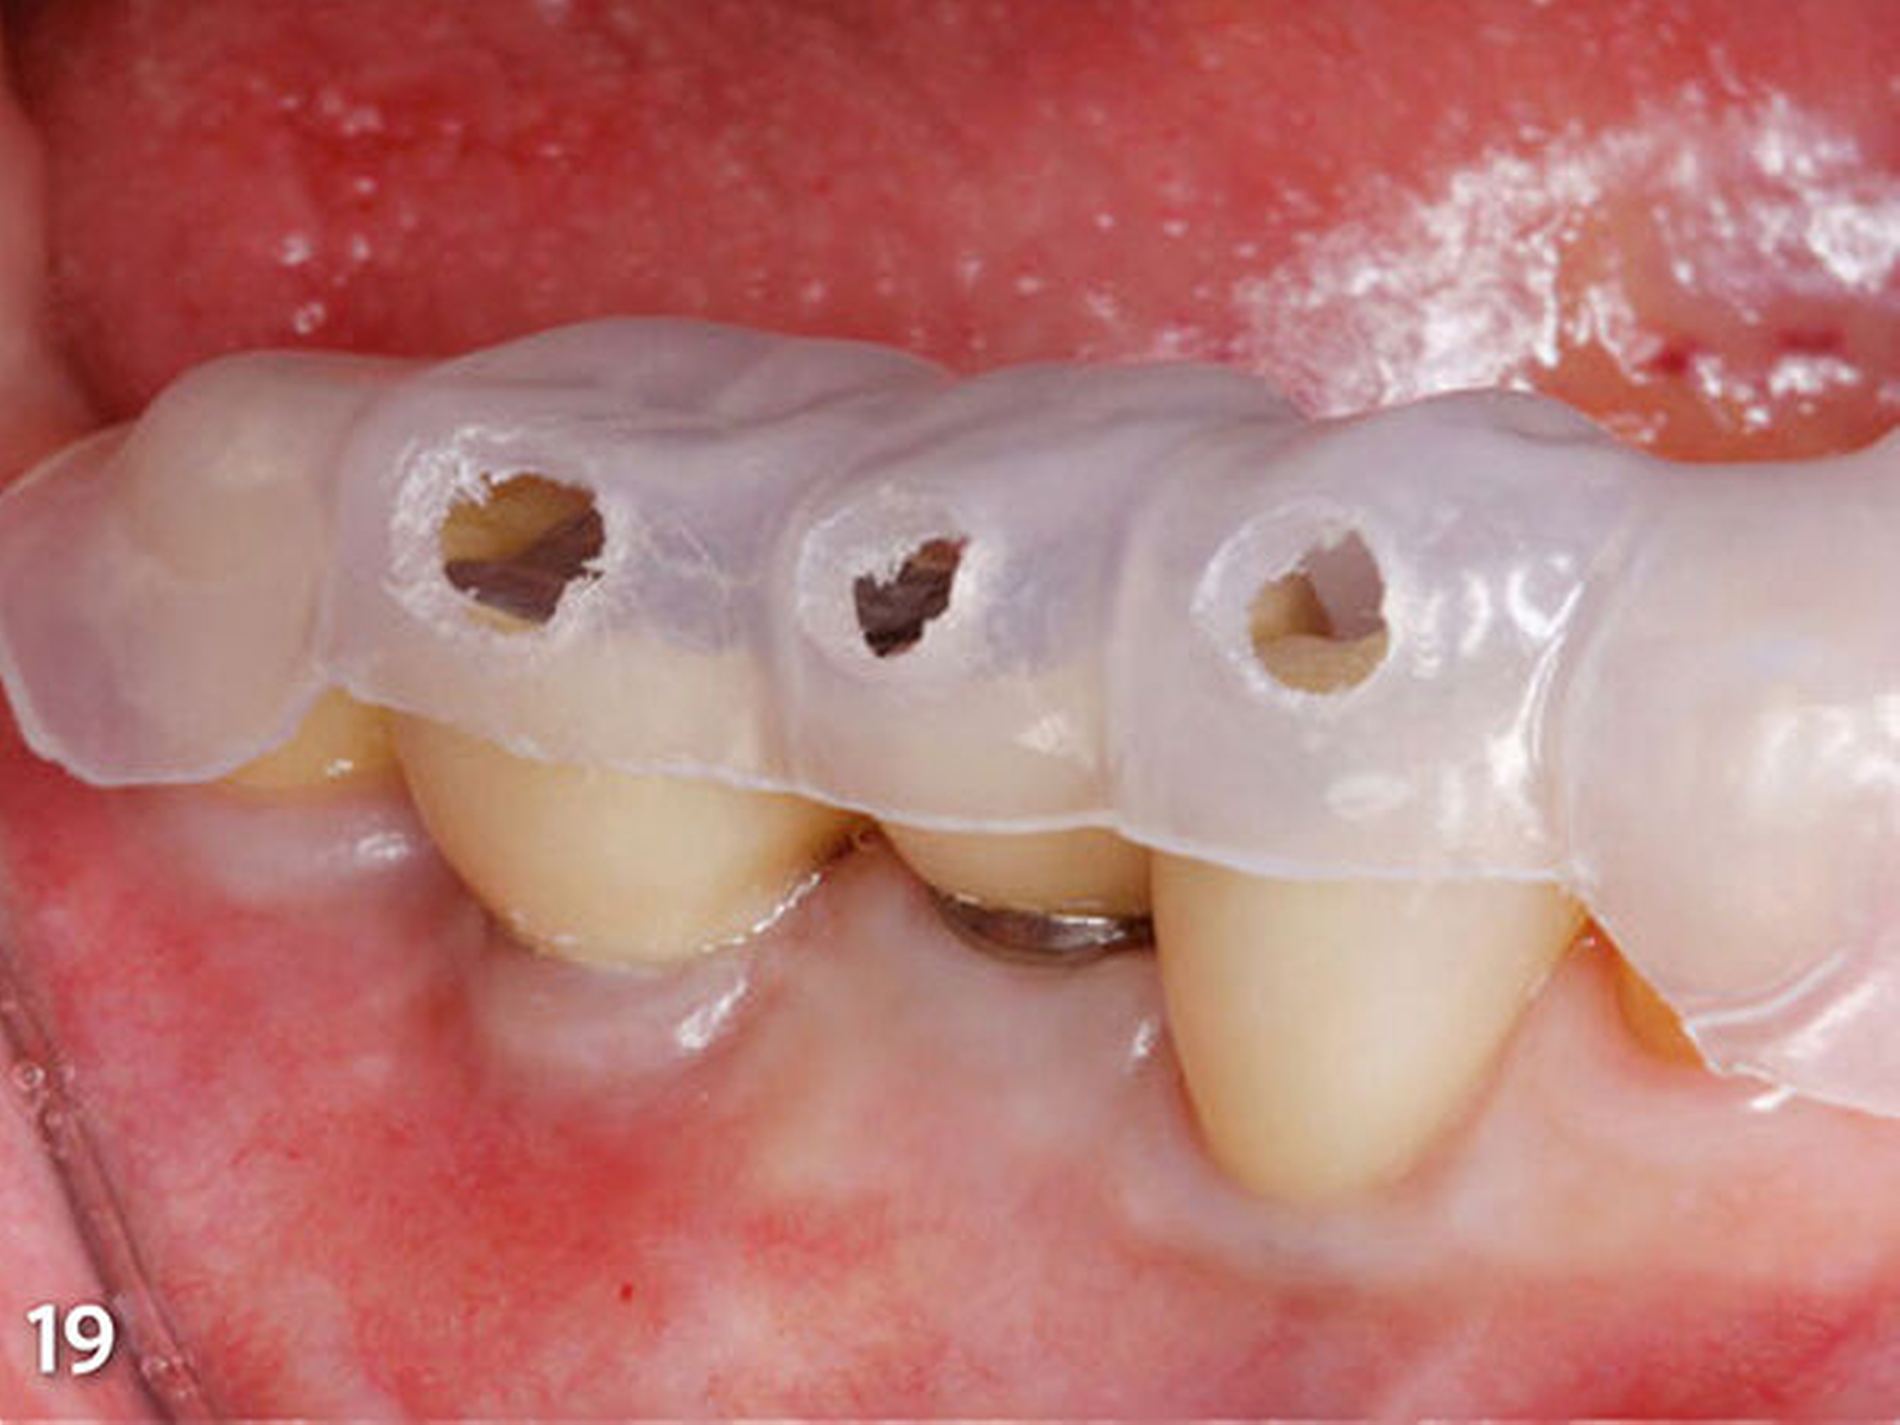

Im dritten und letzten Schritt wurde das Wax-up um die Rekonstruktion der inzisalen Anteile der Frontzähne des Unterkiefers (33 bis 43) erweitert (Abb.16). Die nachfolgend angefertigte dritte Übertragungsschiene (Schiene 3) kann später im Mund an den bereits aufgebauten Seitenzähnen definiert abgestützt werden. Der Dupliervorgang und die Schienenherstellung erfolgten in gleicher Art und Weise wie zuvor beschrieben (Abb.17). An den vestibulären Flächen der Schienen wurden im zahntechnischen Labor für jeden einzelnen aufzubauenden Zahn in vertikal und horizontal mittiger Position der Wachsaufbauten kreisförmige Perforationen als Einspritzöffnungen angebracht.

Diese orientierten sich im Durchmesser an der Auslassöffnung der Kompositkompulen des Materials, das in der folgenden zahnärztlichen Sitzung für den intraoralen Aufbau verwendet werden sollte (Abb.18 und 19). An den oralen Bereichen jedes aufzubauenden Zahnes wurden ebenfalls Perforationen (Entlüftungsöffnungen) an gleicher Lokalisation wie bukkal vorgenommen, um dem überschüssig eingebrachten Kompositmaterial einen leichten und vor allem in der Richtung gesteuerten Abfluss zu ermöglichen. Zuletzt wurde an einem Duplikat des Unterkiefermodells der Ausgangssituation noch eine Schiene für den Schutz der Weichgewebe während der intraoralen Konditionierung der Zahnoberflächen mit einem Sandstrahlgerät angefertigt.

Vierte zahnärztliche Sitzung: Für die bessere Handhabbarkeit wurden die beiden ersten Schienen (Schiene1 und2) zum Aufbau der Seitenzähne im Bereich der Front jeweils in eine linke und eine rechte Hälfte getrennt. Das erste Schienensegment (Schiene1) wurde intraoral auf seinen perfekten spannungsfreien Sitz und die eindeutige Abstützung am letzten Molaren und im Frontzahnsegment hin kontrolliert (Abb.18). Ebenso wurde die korrekte Lage der bukkalen Einspritzöffnungen verifiziert (Abb.19).